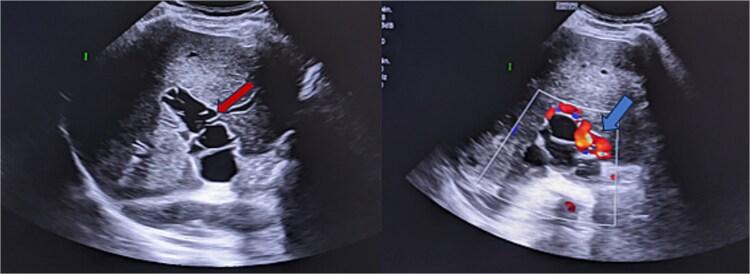

Hydatidosis, caused by , is a widespread parasitic disease, especially in livestock areas. In Morocco, it is hyperendemic and poses a major health concern. The liver and lungs are the most affected organs, but portal vein involvement is extremely rare, with only eight reported cases. We present a 56-year-old man with a recurrent hepatic hydatid cyst, three years after a left hepatectomy. Imaging revealed hydatid thrombosis of the portal vein, a rare complication requiring distinct management from typical venous thrombosis.

由……引起的包虫病是一种广泛传播的寄生虫病,尤其在牧区。在摩洛哥,它是高度流行的,并且是一个主要的健康问题。肝脏和肺是受影响最严重的器官,但门静脉受累极为罕见,仅有八例报告病例。我们报告一例56岁男性,在左肝切除术后三年出现复发性肝包虫囊肿。影像学检查显示门静脉包虫血栓形成,这是一种罕见的并发症,需要与典型的静脉血栓形成进行不同的处理。 (原文中“caused by ”后缺少具体病因信息)